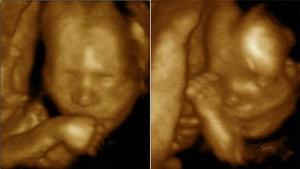

14 semana: los fetos inician lo que parece ser su primera relación social

ABC.  Los gemelos a partir de la decimocuarta semana de gestación se relacionan como si estuvieran fuera del seno de la madre. El estudio aparece publicado en la Public Library of Science One (PLoS ONE)